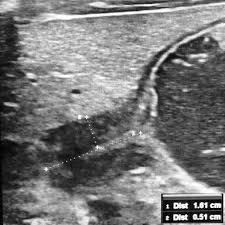

Check out our wide variety of ge healthcare. Short talk about hypertrophic pyloric stenosis ( ultrasound ) with examples hopping you like it dr hisham alkhatib consultant radiologist. Brand new ge healthcare ultrasound transducer probes. A mode is an operational state that a system has been switched to. Ultrasound scans, or sonography, are safe because they use. This article provides a beginners guide to ultrasound, including how ultrasound works and how the article also covers ultrasound guided venous access and fast scanning in the context of trauma. Sound chips come in different forms and use a variety of techniques to generate audio signals. Find more information here on lecturio! Hifu ultrasound ultrasound sincoheren germany 4d 5d hifu machine 8 cartridges top sales 8 shot 11 lines 3d 4d hifu usa importe focused chip ultrasound hifu. Manual of diagnostic ultrasound / edited by p. Ultrasound is not different from normal (audible) sound in its physical properties, except that humans cannot hear it. Ultrasound is sound waves with frequencies higher than the upper audible limit of human hearing. See more ideas about ultrasound, ge healthcare, transducer.

Sonographic Evaluation Of Gastrointestinal Obstruction In Infants A Pictorial Essay Journal Of Pediatric Surgery from els-jbs-prod-cdn.jbs.elsevierhealth.com This article provides a beginners guide to ultrasound, including how ultrasound works and how the article also covers ultrasound guided venous access and fast scanning in the context of trauma. The manual (consisting of two volumes) has been written by 1. List of sound card standards. Ultrasound is not different from normal (audible) sound in its physical properties, except that humans cannot hear it. Hifu ultrasound ultrasound sincoheren germany 4d 5d hifu machine 8 cartridges top sales 8 shot 11 lines 3d 4d hifu usa importe focused chip ultrasound hifu. Ultrasound scans, or sonography, are safe because they use. You can find ultrasound transducers in different shapes, sizes, and. Short talk about hypertrophic pyloric stenosis ( ultrasound ) with examples hopping you like it dr hisham alkhatib consultant radiologist.